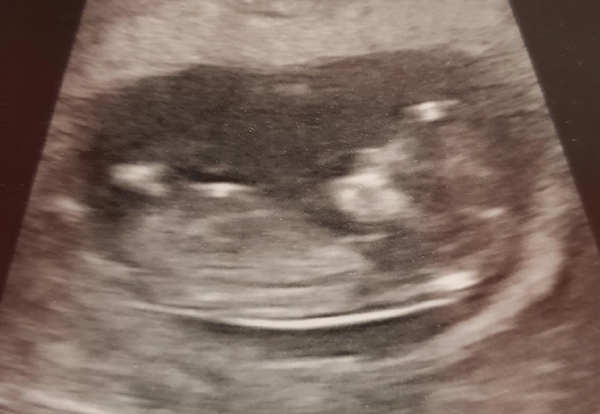

Today is the best day! Say hello to baby Fridge!! 11+6. Could not be more thrilled!!

Congrats fridge! What a fantastic scan pic :)

Shut omg what a beautiful scan pic 😍😍

Thanks ☺️ I've not allowed myself to get too excited up until now, but it's all brimming over now!

Yay congrats @Fridge! Wow - what an amazing pic! xx

Eeeek! Congratulations Fridge that is amazing picture! Baby Fridge looks so active!

Oh wow Fridge that's an amazing picture!! Well worth the full bladder!! Congratulations Grin

Ahhhh @ShutTheFridgeUp look at those long legs!! What a beautiful scan picture!

ShutTheFridgeUp That is an amazing quality photo. Look at those long legs